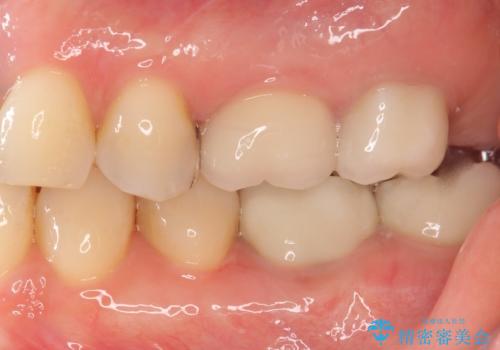

治療後はしみなくなり、違和感のない自然な咬み心地にご満足頂けました。

「割れる心配のないゴールドにしたいけれど、目立ってしまうかしら...」と心配されており、不要に歯質を削合しないよう注意を払い最小限の大きさのインレーを装着したところ、「あまり目立たなくて良かった!」とおっしゃって下さいました。